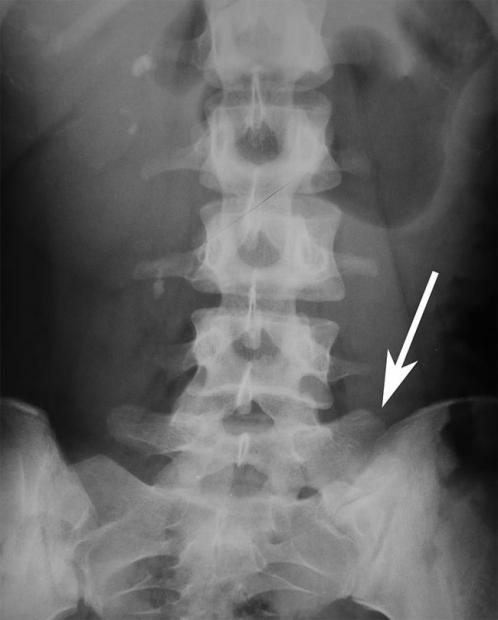

Bảo sao mà nhiều người hay bị đau đốt sống vùng thắt lưng, vị trí này phải chịu nhiều áp lực thế cơ mà.

Không giống như những thứ được thiết kế một cách thận trọng, sự tiến hóa của các loài vật không nhằm hướng đến sự hoàn mỹ, mà chỉ cần khả năng tự thích nghi là đủ. Hơn nữa, tiến hóa không thể bắt đầu từ hư không, mà luôn phải có điểm xuất phát cho tất cả các loài, và điều này dễ dẫn đến những đặc tính không còn cần thiết nữa từ tổ tiên bị sót lại (Như chuyện răng khôn thích mọc lệch chẳng hạn).